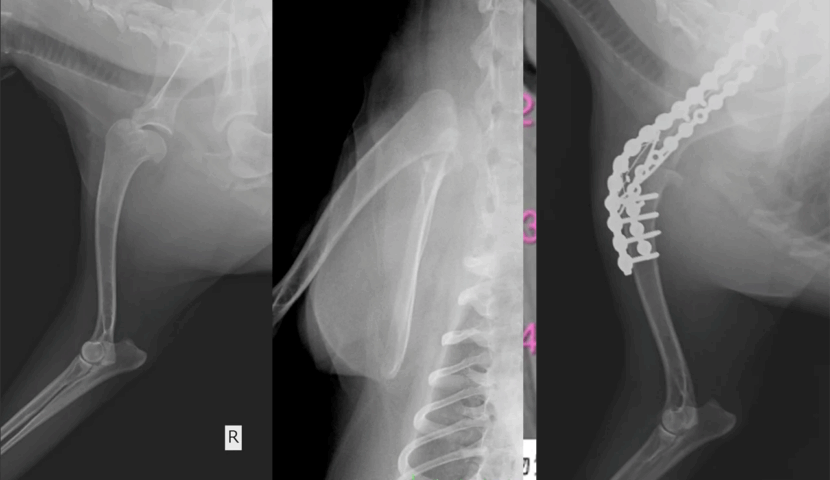

シェットランド・シープドック 右肩関節内方亜脱臼

シェットランド・シープドック 13歳

3ヶ月前から右前肢が歩きづらそうにしていたが、徐々に悪化してきた

右前肢負重性跛行

・整形外科学的検査・レントゲン検査

右肩関節内方亜脱臼

レントゲン撮影をすると右肩関節の内方亜脱臼と変形性関節症を呈しており、肩関節を整復する手術では術後に痛みが残ってしまうと判断されたため肩関節固定術を実施しました。

術後に2週間〜1ヶ月のご自宅での安静が必要になりますが、その後順調に歩様の改善を認めました。